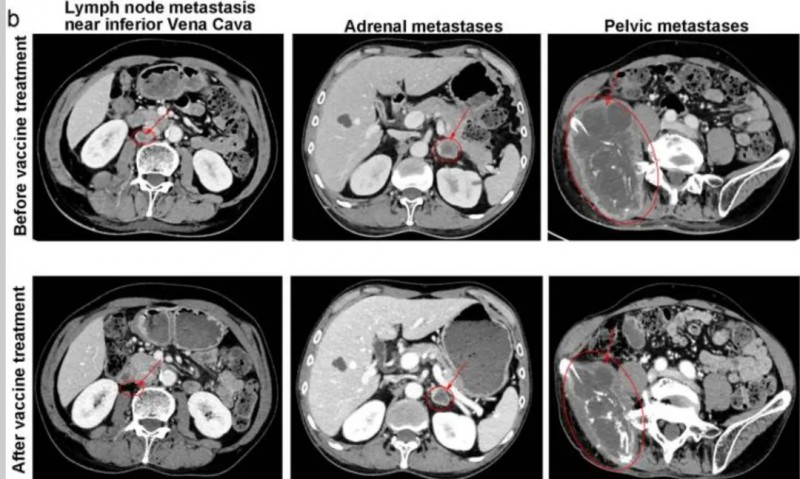

肺腺癌:5剂疫苗注射后肿瘤显著消退

这位幸运的患者既往接受三线化疗和放疗均失败,但在使用Neo-DCVac后7.6个月内未出现任何疾病进展迹象。在五剂个性化Neo-DCVac免疫治疗之前和之后进行CT扫描显示肿瘤靶病灶显著消退。

肺腺癌:肿瘤缩小29%

这位患者同样也经历三线化疗、放疗和PD-1抑制剂治疗失败,在Neo-DCVac治疗后,肿瘤靶病灶缩小了29%。